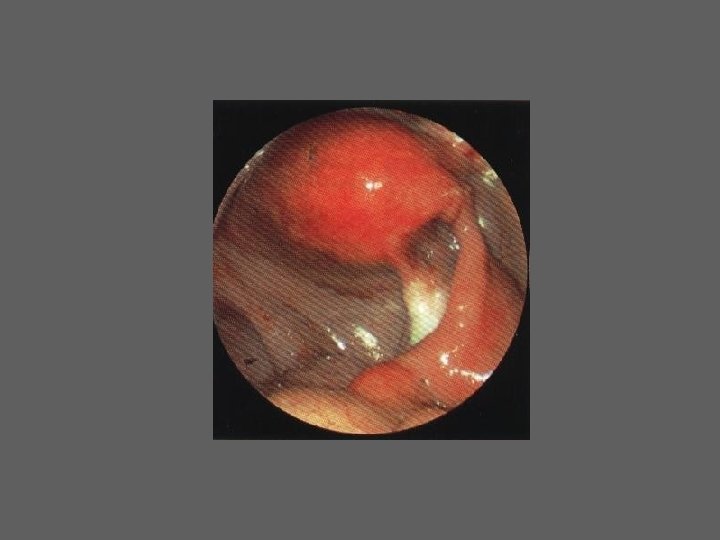

HISTEROSCOPIA - INDICAÇÕES Todas a situações em que se julgue vantajosa uma visualização completa da cavidade uterina, em particular: – Metrorragias – Dismenorreia adquirida – Infertilidade – Abortamentos de repetição e parto pré-termo – HSG anormal – DIU “perdido” – GIFT e ZIFT – Tratamento cirúrgico da patologia intracavitária: ● pólipos, miomas, septos, sinéquias, recessões endometriais ● baixos custos, reduzida morbilidade